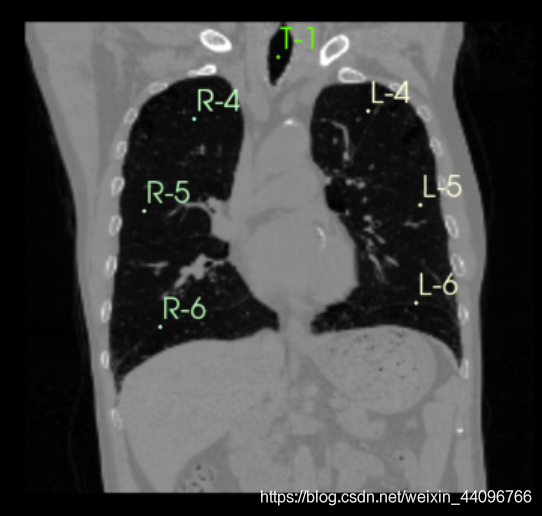

肺部分割

- 进入插件

- 点击start,根据提示在左、右肺、气管处标点后点击apply

分割出来的区域可以根据需要在Segment Editor中手动调整。